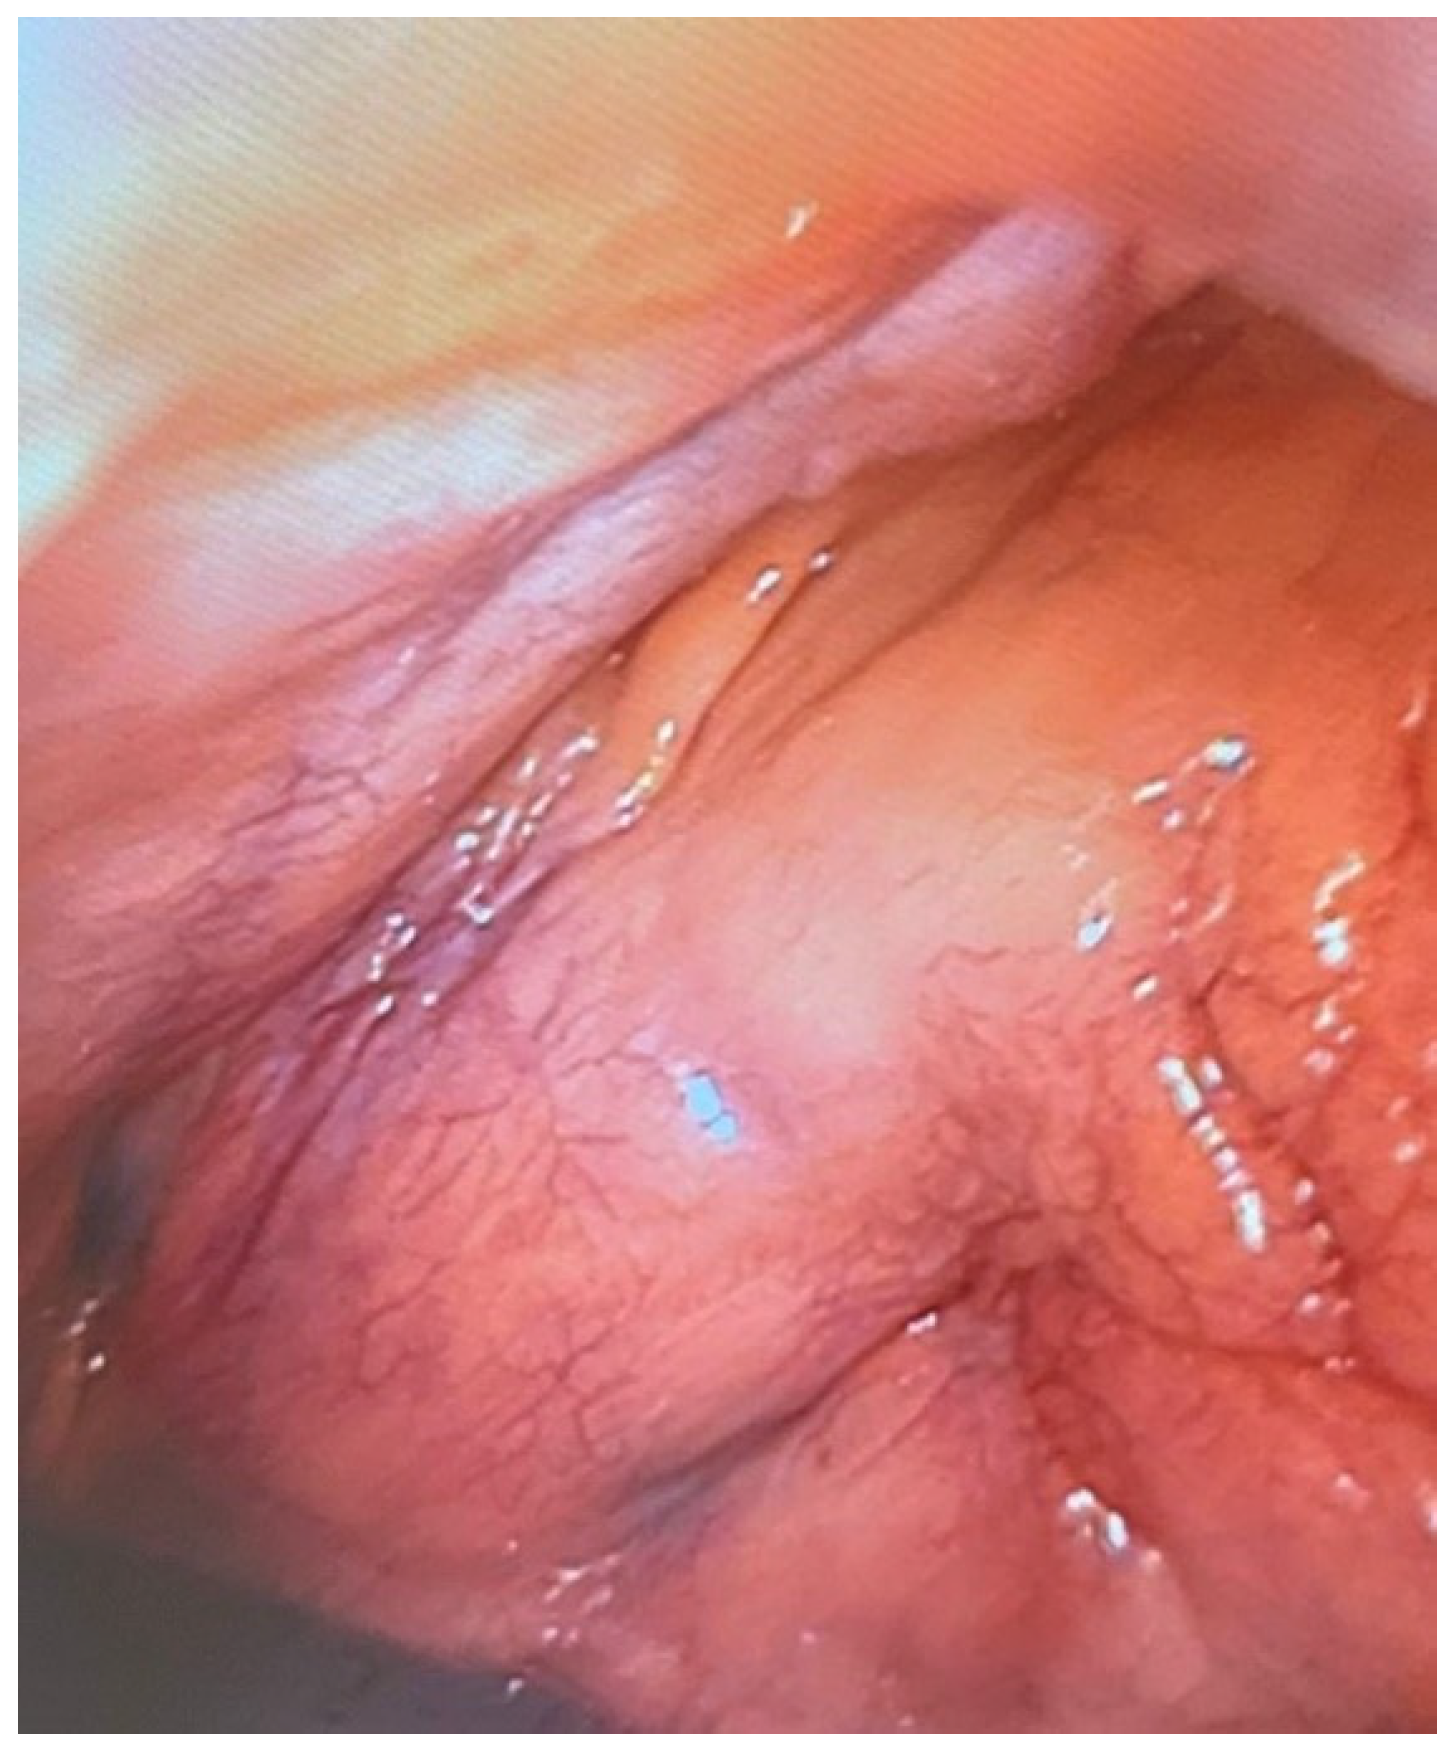

3.2. Establishing a Procedure for Minimally Invasive Post-Mortem Diagnostics Using Endoscopic Techniques

3.3. Clinical Efficiency